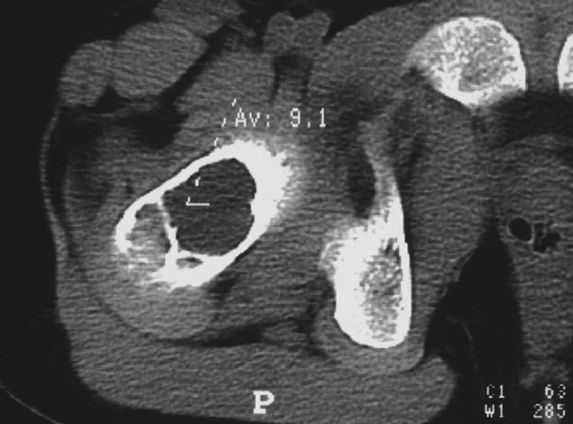

肿瘤内液 - 液平面

肿瘤内液-液平面多数是病灶内囊变出血所致,MRI T2W1 为上部呈高信号下部呈中低信号的液-液平面。CT 可为上部低密度下部高密度的液-液平面(图 32)。液-液平面常见于动脉瘤样骨囊肿、但也可见于骨内腱鞘囊肿(图 33)、囊性血管瘤病等其他肿瘤和肿瘤样病变。

图片

图 32.肿瘤内液-液平面:动脉瘤样骨囊肿